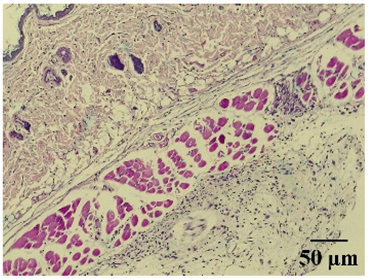

| 100× | 400× | Description | |

|---|---|---|---|

| Normal | ![]() | ![]() | Minimal leukocyte infiltration in the dermis, hypodermis, and subcutaneous tissue. Minimal leukocyte infiltration and slight alteration in the air pouch membrane thickness. |

| Control | ![]() | ![]() | Moderate presence of erythrocytes in subcutaneous tissue. Moderate leukocyte infiltration in the dermis, hypodermis, and muscle layer. Presence of eosinophils at the subcutaneous and muscular levels. Abundant leukocyte infiltration and intense alteration of the air pouch membrane thickness. |

| Indomethacin | ![]() | ![]() | Moderate leukocyte infiltration in the dermis and subcutaneous tissue. Moderate leukocyte infiltration and moderate alteration in the thickness of the air pouch membrane. |

| Mature hydrophilic 500 | ![]() | ![]() | Low leukocyte infiltration in the dermis and subcutaneous tissue. Low leukocyte infiltration and slight alteration in the thickness of the air pouch membrane. |

| Mature hydrophilic 1000 | ![]() | ![]() | Moderate infiltration of leukocytes in the dermis and subcutaneous tissue. Moderate leukocyte infiltration and moderate alteration in the thickness of the air pouch membrane. |